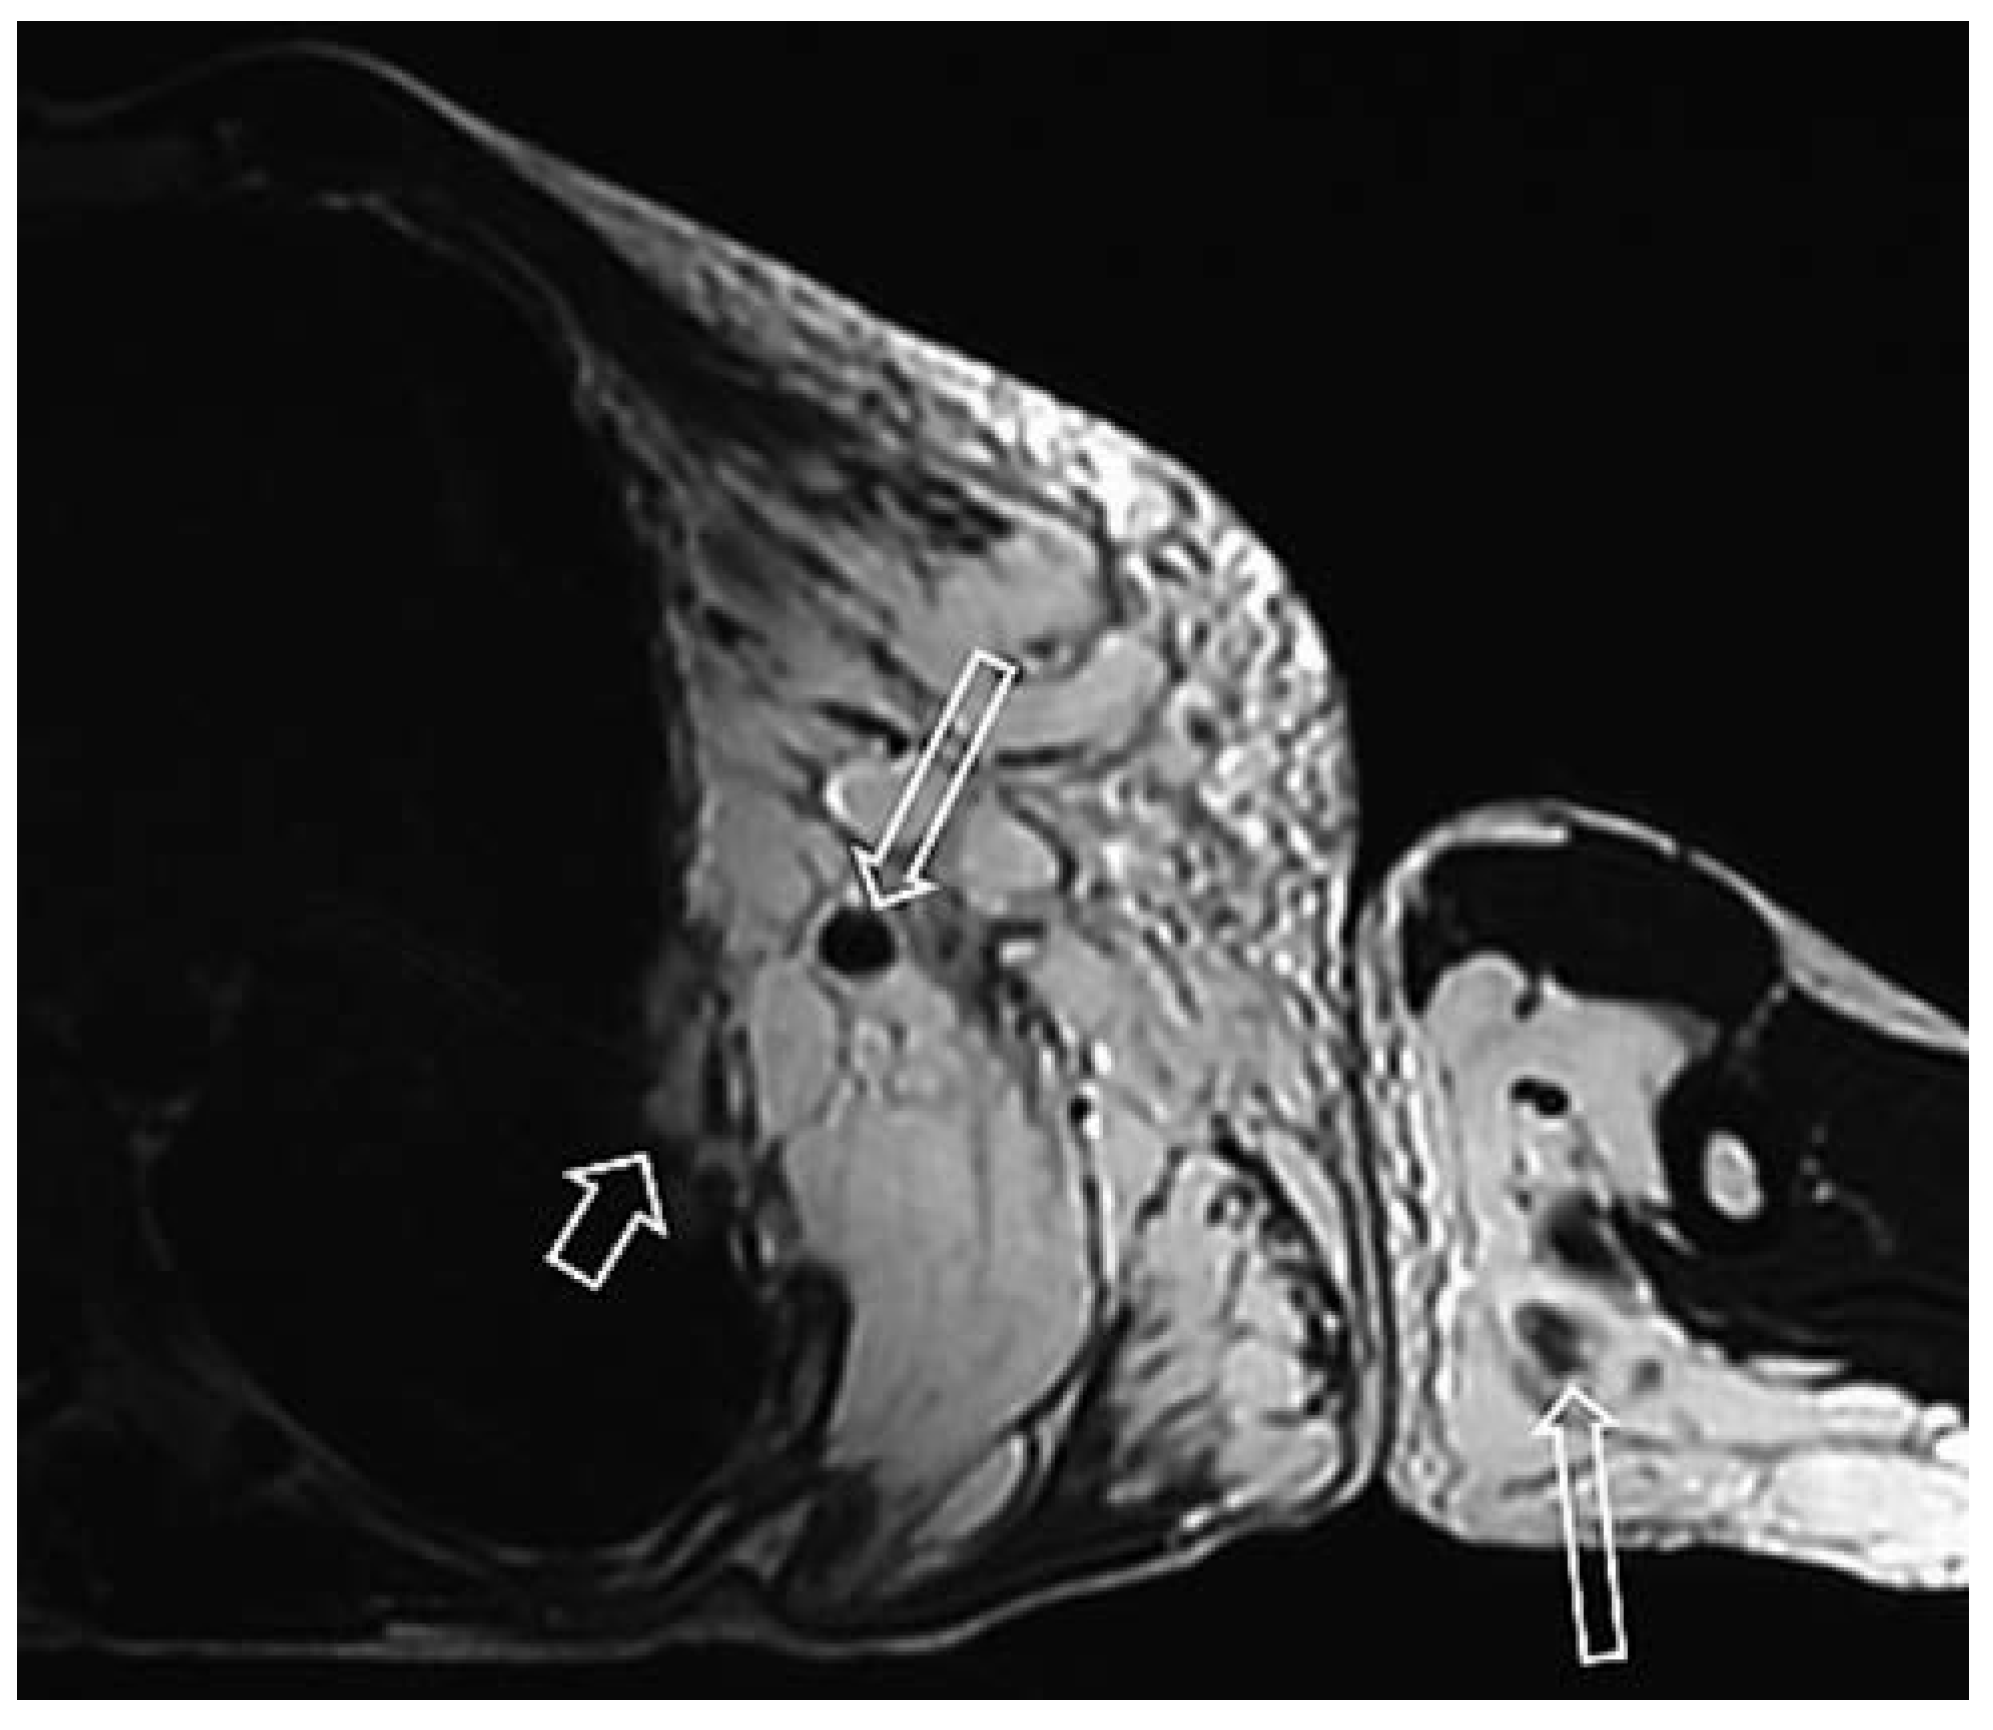

Venöse Malformationen

- Jans, L.; et al. MRI demonstrates the extension of juxta-articular venous malformation of the knee and correlates with joint changes. Eur Radiol. 2010, 20, 1792–1798. [Google Scholar] [CrossRef]